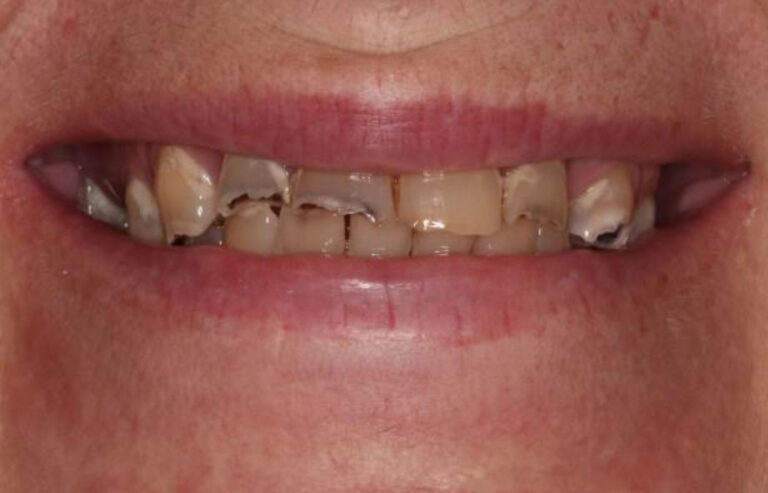

Our Full-Arch Dental Implant Process